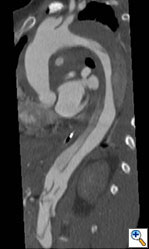

Figure 1e. Oblique sagittal CT reconstruction demonstrates the Type A dissection is complex with multiple fenestrations in the abdomen. Note bovine arch anatomy.